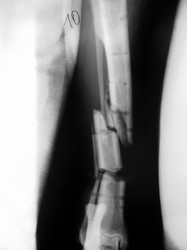

Fijación Externa

PRÁCTICAS CURSO DE FIJACIÓN EXTERNA PERFECCIONAMIENTO.

Híbrido.